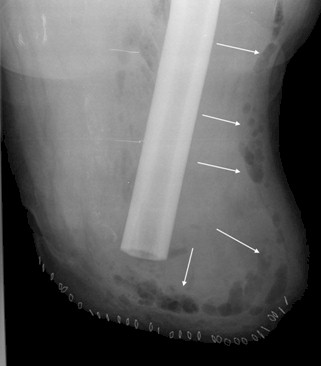

Aunque inicialmente se sospechó un foco urinario como causante del cuadro tras el hallazgo de piuria y bacteriuria en un sedimento de orina, en la exploración destacaba crepitación a nivel del muñón quirúrgico. Se solicitó entonces una radiografía simple del mismo donde se observó existencia de gas en partes blandas (imagen 1: flechas) lo que se confirma en una Tomografía Computerizada (TAC), donde se observa afectación de toda la musculatura del miembro inferior izquierdo hasta la raíz del muslo con gas en su interior (imagen 2: flechas). Se instauró tratamiento antibiótico de amplio espectro que incluía Penicilina G y Clindamicina, y tratamiento del Shock Séptico según los criterios de la Conferencia Consenso de la Sepsis Surviving Campaign (1).

Figura 1